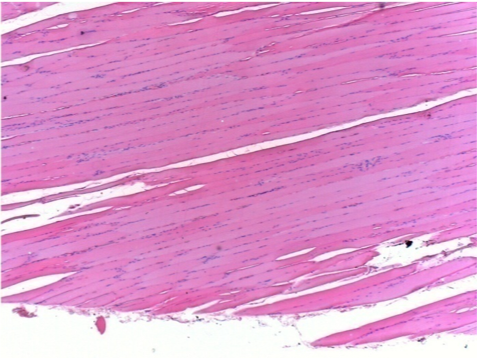

3 mesi dopo Iniezione di Endopeel

Scatola Nr 4

3 mesi (Giorno90) dopo iniezione 0.1ml di Endopeel nel muscolo pretibiale destro ( Dx)

Sx : Controllo-100x-Giorno90

Dx:100x-Giorno90